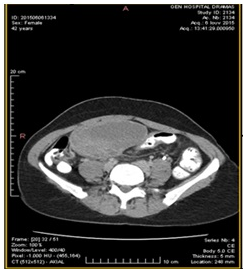

The CT (Figures 2–4) showed a large, multi-spaced, clearly defined circumscribed mass composed of cystic and solid components with a volume of 400milliliters (maximum diameter: 10.8cm).The mass extended up to the level of the right distal ureter without infiltrating it. Normal lymph nodes (para-aortic space) were noted. No other pathological findings were detected in the abdomen.

Figure 2 CT abdomen (transverse plane) depicts the cyst presence in the right ovary (10.5cm×7cm) with solid and cystic elements.